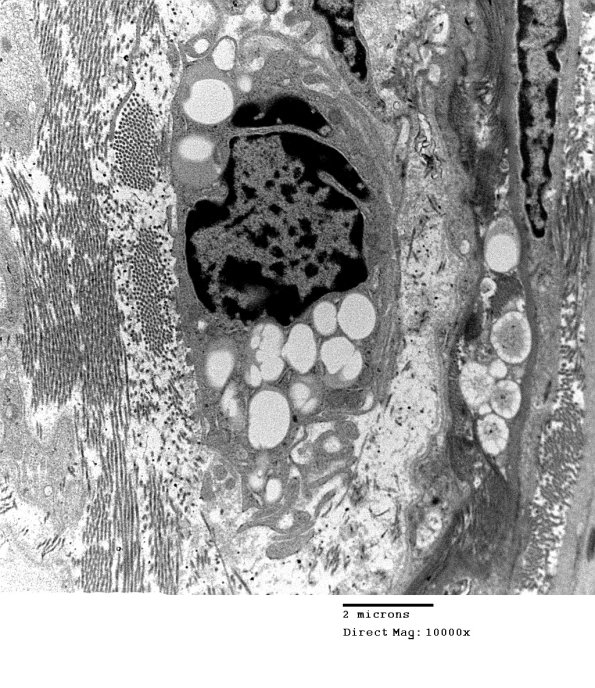

This macrophage contains vacuoles and maintains significant numbers of ramified processes.